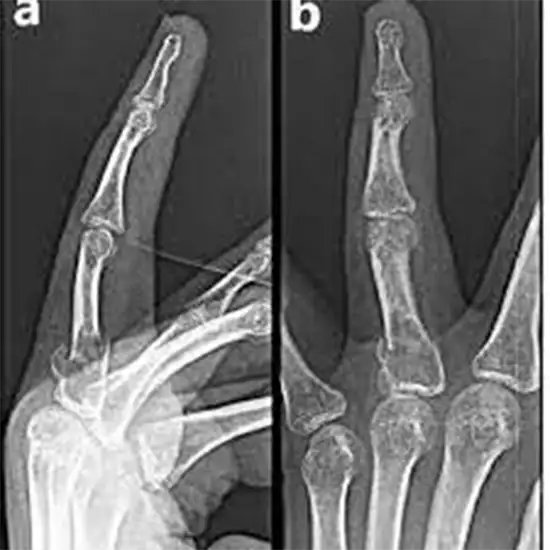

Finger X-ray Doctors prescribe AP and LAT on the left side to determine the source of finger discomfort, soreness, swelling, or deformity. The LAT view shows the finger in the lateral position. The AP (or anteroposterior) view shows the beams passing from front to back. The AP view is used to determine which finger is being photographed with respect to neighboring fingers in the field of vision.